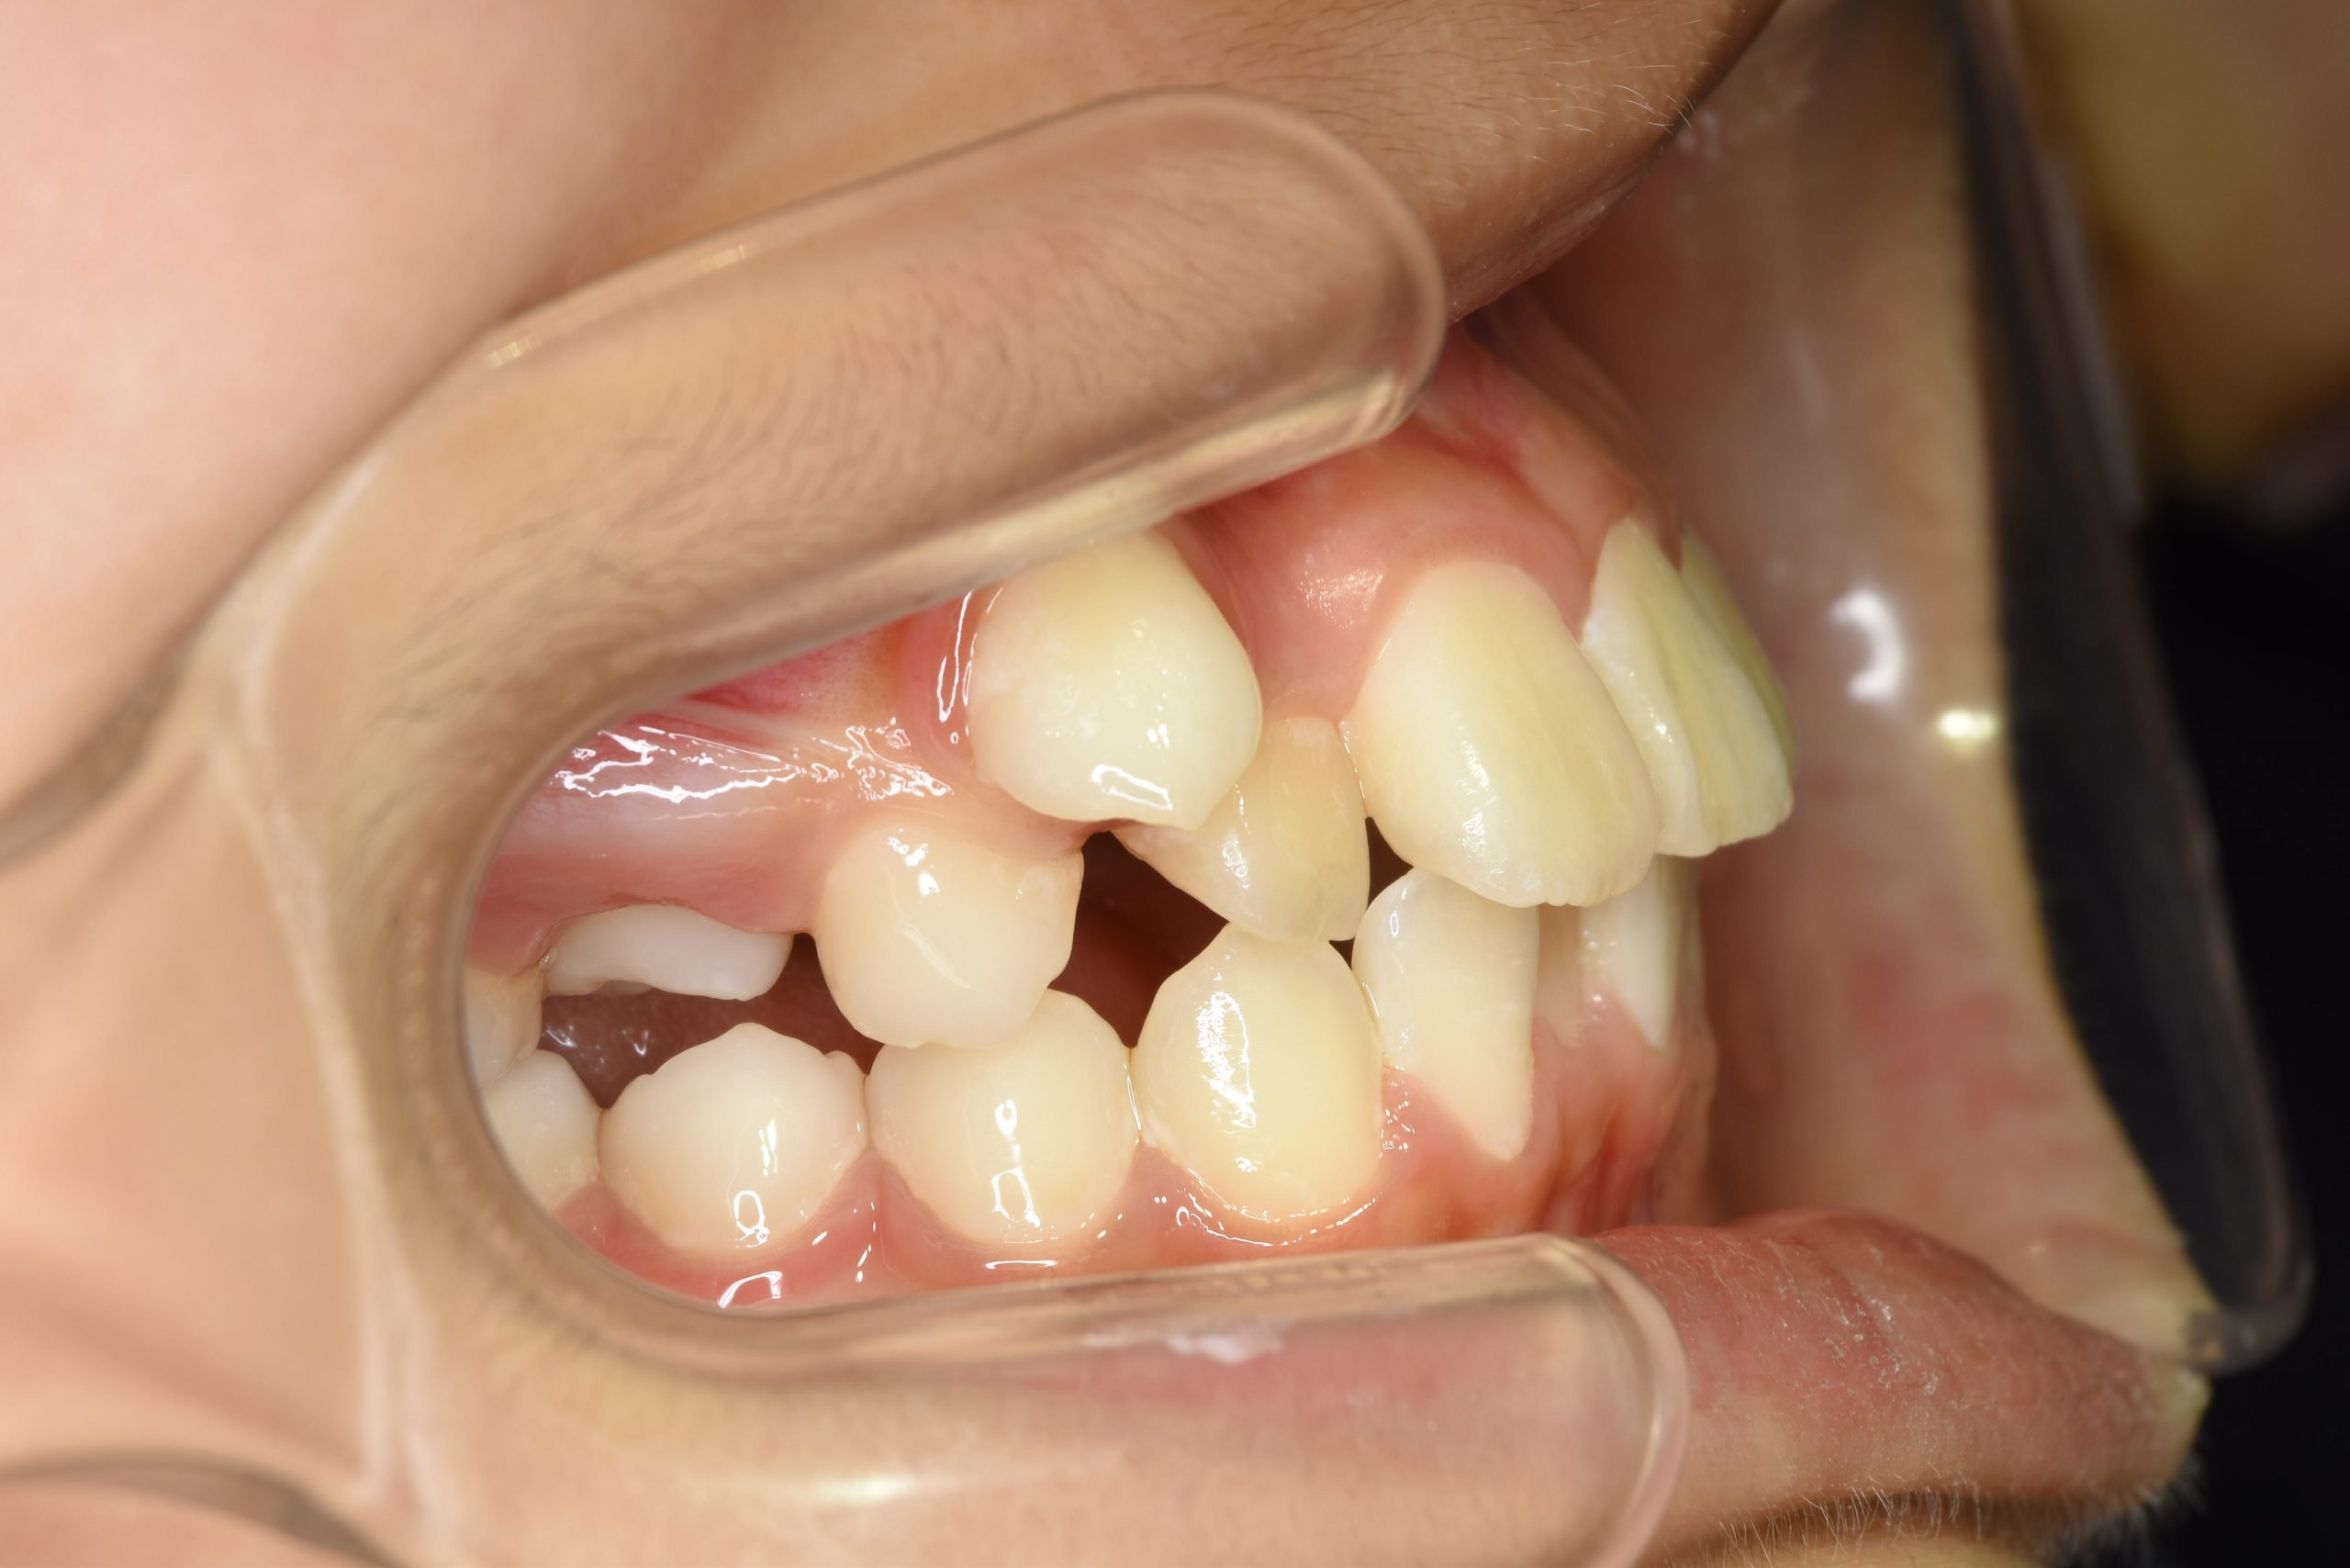

ビフォー

ワイヤー矯正治療|症例_1324

主訴 下顎が出ている

施術内容 MSEと下顎リンガルアーチを用いて上下顎骨を拡大した。

その後マルチブラケット装置を用いて非抜歯で歯牙を配列し、良好な咬合を獲得した。